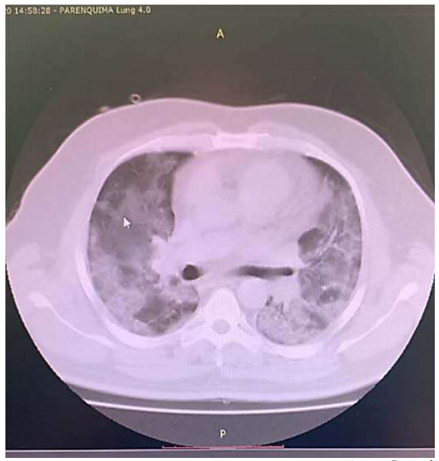

Um paciente de 68 anos de idade, com RT PCR para Sars-CoV-2 reagente (VR = não reagente), evolui com astenia, inapetência, tosse seca e coriza nasal. Realiza exames de imagem, no quinto dia de doença, em tomógrafo de alta definição, em que foram descritas lesões em vidro fosco bilaterais, correspondendo a 25% dos pulmões, podendo estarem associadas a processo inflamatório/infeccioso viral. Segue em acompanhamento domiciliar da doença. No 12º dia de doença, o paciente retorna com rouquidão, cianose de extremidades, apresentando febre de 38 o C e desconforto respiratório com uso de musculatura acessória. Verificam-se ausculta pulmonar com tórax silente, SatO2 = 78% com 15 litros / minuto de oxigênio em máscara facial com reservatório, PA = 87 mmHg x 43 mmHg, FC = 123 bpm e FR = 52 irpm. Os exames indicaram os seguintes resultados: leucograma = 5.400, sem desvios; PCR (proteína C reativa) = 356 (VR = abaixo de 6); ferritina = 11.458 ng/mL (VR = 20 ng/mL a 330 ng/mL); dímero -D = 26 mcg/mL (VR = 0,5 mcg/mL); gasometria pH = 7,109 (VR = 7,35 a 7,45); PaO2 = 53,8 mmHg (VR = 80 mmHg a 100 mmHg); PaCO2 = 104,6 mmHg (VR = 35 mmHg – 45 mmHg); HCO3 = 21 mmol/L (VR = 21 mmol/L a 28 mmol/L); SaO2 = 76,7 % (VR = 95% a 99%). Foi realizada nova tomografia do paciente, cuja imagem parcial pode ser observada a seguir.

Com base nesse caso clínico, na imagem da tomografia apresentada e nos conhecimentos médicos correlatos, julgue os itens a seguir.